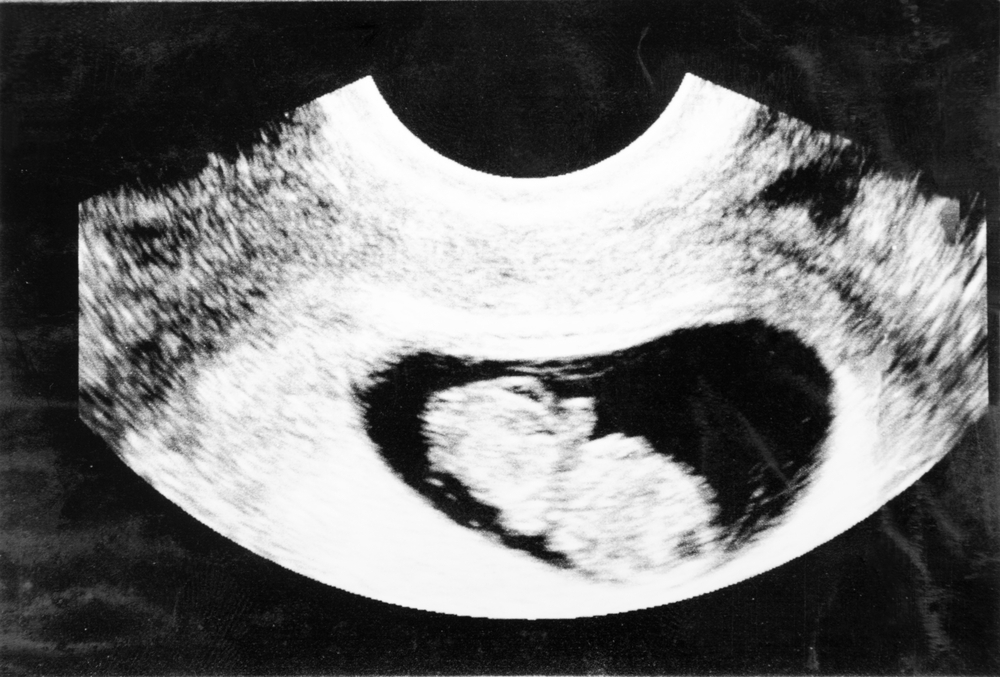

Your baby is undergoing a transition from an embryo to the fetal stage at 9 weeks pregnant. Your baby grows rapidly at the 9th week of pregnancy, i.e. limb and organ development occur at this stage. You can also hear the heartbeat of your baby with the help of a Doppler device.